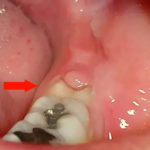

Жалобы на то, что целый зуб зарос десной, не всегда описывают реальное положение вещей. Такой зуб часто лишь выглядит здоровым, но при тщательном стоматологическом осмотре в нем обнаруживается кариозная полость в участке, который не просматривается без специальных инструментов. Чаще всего гиперплазия десен развивается при контактном кариесе или кариесе шейки зуба.

В первом случае интенсивный рост тканей начинается с десневого сосочка — приподнятого и заостренного участка десны, который «вклинивается» между двумя соседними зубами. Во втором случае гипоплазия десны берет свое начало на фронтальной поверхности в том месте, где находится кариозная полость — зуб начинает зарастать снизу вверх, что наиболее заметно по сравнению с высотой соседних десен.

В обоих случаях причиной этого состояния становится воспалительный и инфекционный процесс в деснах, обусловленный кариесом и присутствием в отдельном участке десны постоянного источника инфекции (кариозной полости).